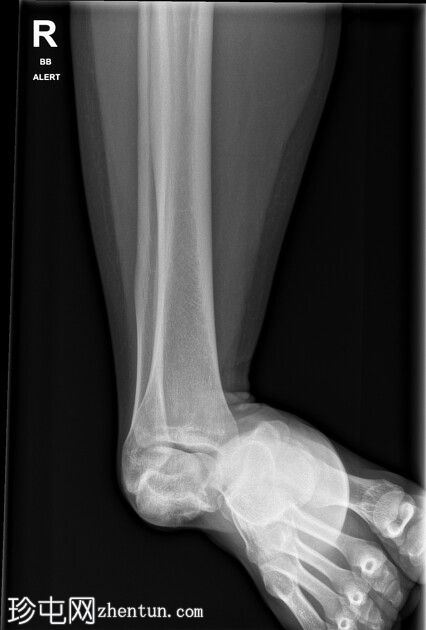

X光片

创伤室仅有单侧正位片。距下骨外侧脱位。未发现骨折。

最初远端脉搏消失。在急诊科镇静下成功复位,远端脉搏恢复。CTA(未提供)显示动脉造影良好,无血管损伤,距骨后突内侧轻微粉碎性骨折。